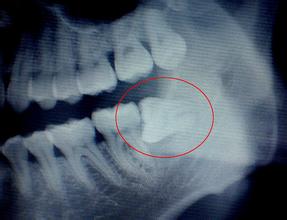

3、如果智齒萌出位置不對,其中,大多數(shù)智齒呈45度左右角頂在第二磨牙上,牙冠中間的容易嵌塞食物,長期如此容易導(dǎo)致第二磨牙發(fā)生牙髓炎。甚至還有可能出現(xiàn)更嚴(yán)重的后果,因為智齒繼續(xù)萌出,受力于第二磨牙,導(dǎo)致牙周炎、牙齒松動情況,必須拔除智齒和第二磨牙,影響到咀嚼功能。